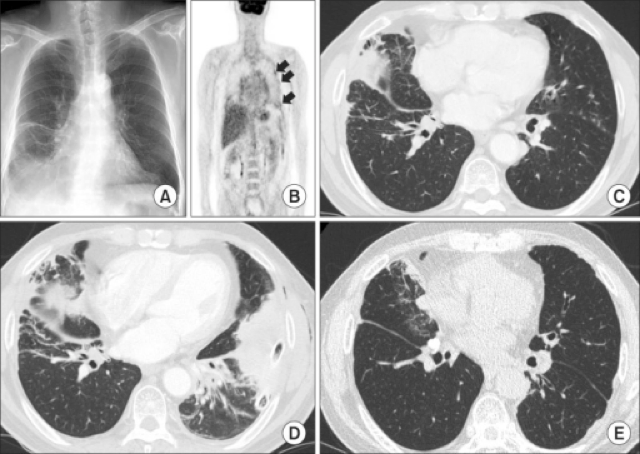

Most cases of lung cancer are associated with. Intrathoracic Manifestations of IgG4-Related Disease | Lim

Intrathoracic Manifestations of IgG4-Related Disease | Lim from pulmonarychronicles.com